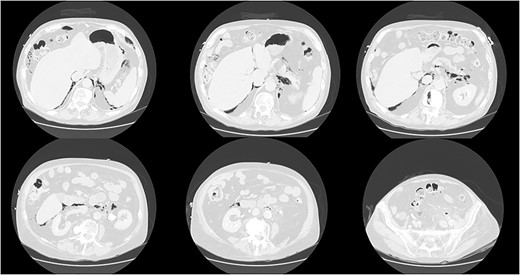

His vitals were stable on presentation. Physical exam was significant for weakness, tachypnea, and wheezing. He had no appreciable subcutaneous emphysema on clinical exam. Workup in the emergency department was remarkable for increased white blood cell count (17.0 K/uL). EKG showed no acute changes and cardiac enzymes were within normal limits. Computed tomography (CT) of the chest, abdomen, and pelvis with contrast was obtained, demonstrating acute sigmoid diverticulitis with extensive retroperitoneal air originating next to the sigmoid colon and multiple small collections of fluid. The pneumoretroperitoneum was continuous with pneumomediastinum and cervical emphysema (Figs 1 and 2). He was diagnosed with perforated diverticulitis and operative intervention was recommended.

CT scan of the abdomen and pelvis demonstrating perforation of the sigmoid colon and free gas in the retroperitoneum and mediastinum.